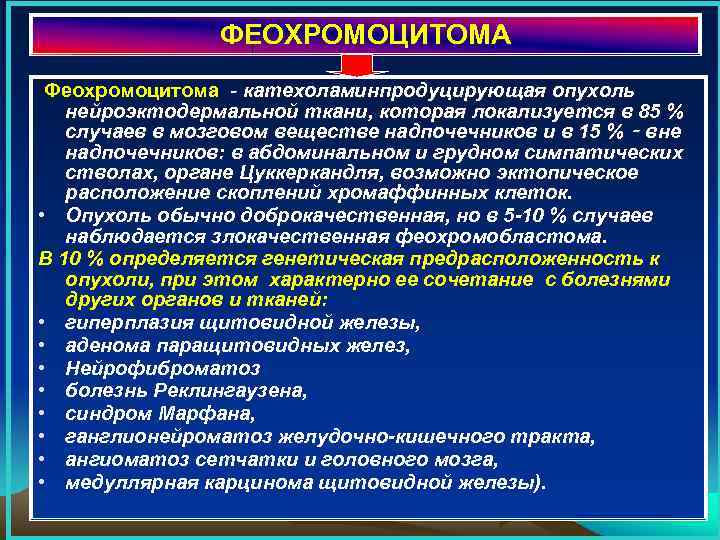

ФЕОХРОМОЦИТОМА Феохромоцитома - катехоламинпродуцирующая опухоль нейроэктодермальной ткани, которая локализуется в 85 % случаев в мозговом веществе надпочечников и в 15 % ‑ вне надпочечников: в абдоминальном и грудном симпатических стволах, органе Цуккеркандля, возможно эктопическое расположение скоплений хромаффинных клеток. • Опухоль обычно доброкачественная, но в 5 -10 % случаев наблюдается злокачественная феохромобластома. В 10 % определяется генетическая предрасположенность к опухоли, при этом характерно ее сочетание с болезнями других органов и тканей: • гиперплазия щитовидной железы, • аденома паращитовидных желез, • Нейрофиброматоз • болезнь Реклингаузена, • синдром Марфана, • ганглионейроматоз желудочно-кишечного тракта, • ангиоматоз сетчатки и головного мозга, • медуллярная карцинома щитовидной железы).

ФЕОХРОМОЦИТОМА Феохромоцитома - катехоламинпродуцирующая опухоль нейроэктодермальной ткани, которая локализуется в 85 % случаев в мозговом веществе надпочечников и в 15 % ‑ вне надпочечников: в абдоминальном и грудном симпатических стволах, органе Цуккеркандля, возможно эктопическое расположение скоплений хромаффинных клеток. • Опухоль обычно доброкачественная, но в 5 -10 % случаев наблюдается злокачественная феохромобластома. В 10 % определяется генетическая предрасположенность к опухоли, при этом характерно ее сочетание с болезнями других органов и тканей: • гиперплазия щитовидной железы, • аденома паращитовидных желез, • Нейрофиброматоз • болезнь Реклингаузена, • синдром Марфана, • ганглионейроматоз желудочно-кишечного тракта, • ангиоматоз сетчатки и головного мозга, • медуллярная карцинома щитовидной железы).